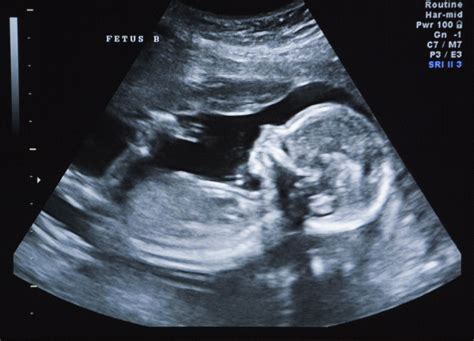

Ori de câte ori vă confruntați cu o schimbare bruscă a sughițului bebelușului, dacă este mai puternic, mai lung sau pur și simplu diferit, apelați la medic, pentru siguranță. Un doppler fetal sau ultrasunetele pot ajuta la diagnosticarea unei probleme.